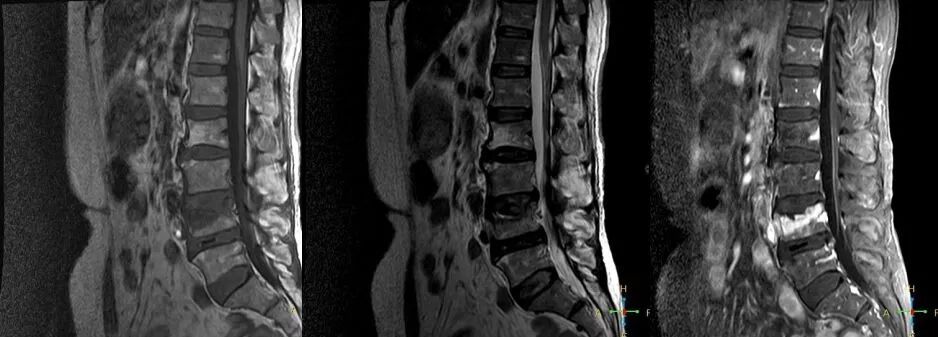

3 恶性压缩性骨折 椎体上下径变窄而前后径增大,椎体后部皮质后突,后角一般表现圆钝,无上翘,常呈球形突出,致椎管狭窄,即膨胀性盘状破坏,硬膜囊和脊髓受压。

——恶性压缩性骨折MR信号特点—— 由于肿瘤组织的侵犯,T1WI上椎体呈弥漫性低信号,T2WI呈高信号,增强扫描呈明显不均匀强化。

转移瘤 椎弓根改变:椎弓根膨大仅见于恶性压缩性骨折,故为其特异性,可作为鉴别诊断的依据。

椎旁软组织肿块:在转移瘤中,受累椎体周围多出现分叶状或肿瘤样软组织肿块,此征象仅见于恶性压缩性骨折。故,椎旁薄环状软组织与瘤样软组织肿块是鉴别骨折性质较有特征性的征象。

4 总结:鉴别诊断 ——良性压缩性骨折—— 楔形或凹陷形 连续性分布 椎间盘增厚双凸状,许莫氏结节 急性期T1WI不均匀低信号 椎体后角翘起突入椎管内 椎体后角回避现象 可伴椎弓根水肿、无膨大 椎旁薄环形软组织影

——恶性压缩性骨折—— 扁平形或倒楔形 跳跃性分布(转移瘤) 椎间盘不受累 T1WI均匀低信号 后角圆钝,膨胀性盘状破坏 椎弓根受累、膨大 椎旁分叶状及肿瘤样软组织肿块